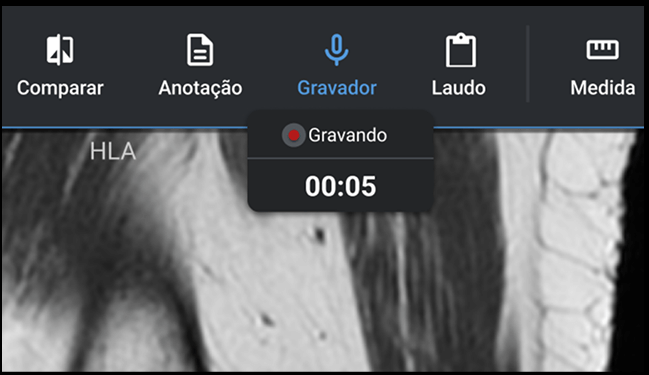

Cree informes mediante reconocimiento de voz, dictado digital y plantillas de informes estándar con solo unos pocos clics. Agregue imágenes y vídeos clave para informes multimedia.

Acceda a imágenes, informes y archivos adjuntos en su teléfono inteligente. Notificar a los pacientes y solicitantes cuando haya un resultado disponible. Inicie sesión a través del CÓDIGO QR para que los pacientes y

solicitantes puedan acceder a los resultados fácilmente.

Acceda a imágenes, informes y archivos adjuntos en su teléfono inteligente. Notificar a los pacientes y solicitantes cuando haya un resultado disponible. Consulte sus resultados desde 1 solo link.